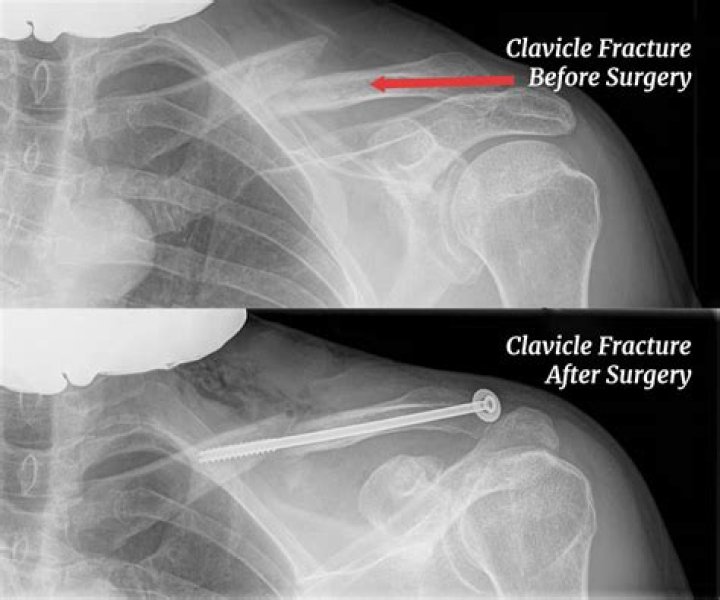

Which clavicle fracture requires surgery?